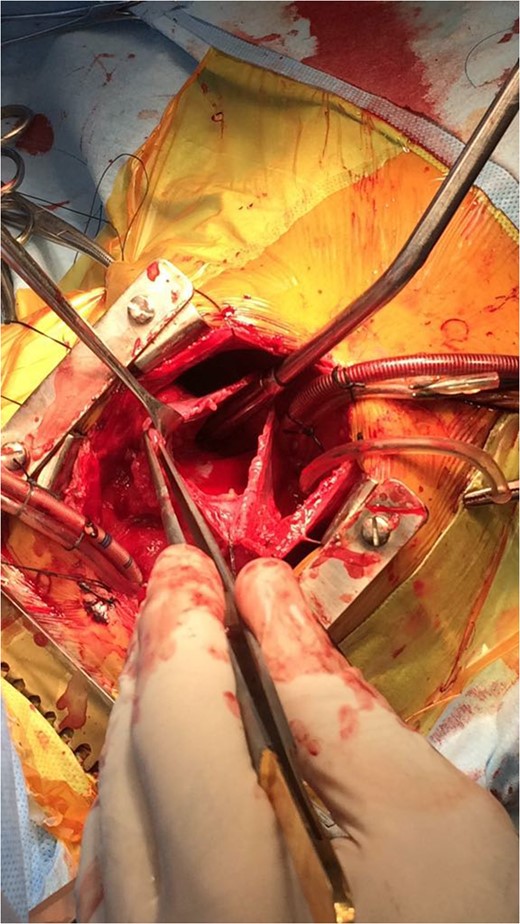

Primary cardiac tumour is a rare entity as secondaries in the heart are more common. A 2-year-old child was having repeated respiratory tract infection with poor oral intake and poor activity for 3 months. His symptoms progressed from New York Heart Association (NYHA) Class II to IV. On evaluation he had an intracardiac mass with extracardiac extension. Emergency tumour excision under deep hypothermic circulatory arrest was performed with provisional diagnosis of sarcoma. But Serum markers, histopathological examination and immunohistochemistry confirmed diagnosis of yolk sac tumour. Postoperative recovery was uneventful and the child was receiving adjuvant chemotherapy. Extensive literature review revealed only four cases of primary intracardiac yolk sac tumour published till date. Our case report is unique, in that intracardiac tumour had extracardiac extension by infiltration through right atrial wall. Previous four reports mention purely intracardiac mass.

A 2-year-old male child was brought to hospital with respiratory distress since last 2 weeks. He was having repeated respiratory tract infection since last 3 months along with poor oral intake and poor activity. His symptoms progressed from New York Heart Association (NYHA) Functional Class II to IV over last 2 weeks. On investigation at another hospital he was diagnosed with intracardiac mass having extracardiac extension. Parents brought the child to our hospital for further management.

Primary cardiac tumour is rare. Only 25% of primary cardiac tumours are malignant. Survival rate for malignant primary cardiac tumours without surgical resection at 9–12 months is only 10%. Sarcomas constitute 75% of malignant primary cardiac tumour. Germ cell tumour is rare. Germ cell tumours are due to abnormal differentiation of foetal germ cells that arise from the foetal yolk sac. Normal migration of these germ cells may cause gonadal tumours, i.e. ovary and testis, whereas abnormal migration produces extragonadal tumours. Most cardiac germ cell tumours are teratomas. Yolk sac tumour is extremely rare. Surgical resection followed by chemotherapy is preferred treatment for yolk sac tumour. Only four cases of primary intracardiac yolk sac tumour are published till date in medical literature. Those are listed in Refs [2–5]. Three other cases of yolk sac tumour are reported but they were extracardiac being in pericardial cavity [6]. We are probably reporting fifth case of primary intracardiac yolk sac tumour.

Our case report is unique, in that intracardiac tumour had extracardiac extension by infiltration through right atrial wall. Previous four reports mention purely intracardiac mass. The rarity in the literature of such pathological occurrence makes our case report very unique.